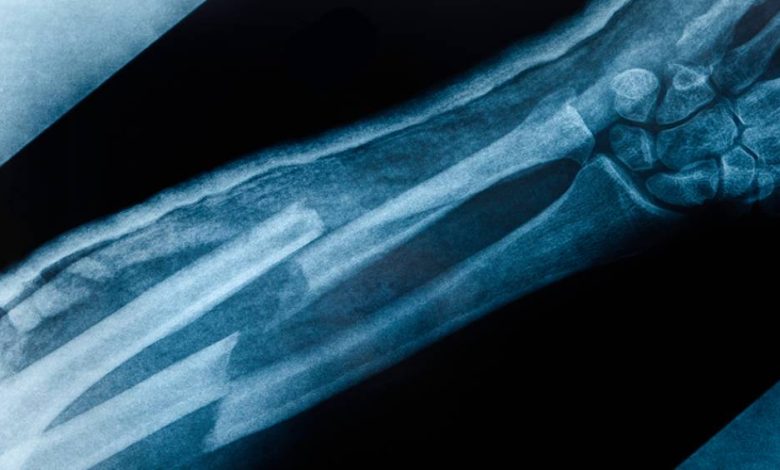

Um grupo de pesquisadores sul-coreanos da Universidade Sungkyunkwan, em Seul, desenvolveu uma ferramenta revolucionária que se assemelha a uma pistola de cola quente, mas com uma função totalmente diferente. Essa tecnologia permite a impressão de enxertos ósseos diretamente sobre fraturas complexas durante cirurgias, proporcionando uma abordagem inovadora e eficaz para casos de trauma de emergência. O dispositivo, que funciona com um filamento de hidroxiapatita e um polímero biodegradável chamado PCL, consegue preencher sulcos irregulares de fraturas a uma temperatura segura para os tecidos vivos. Fonte:Super